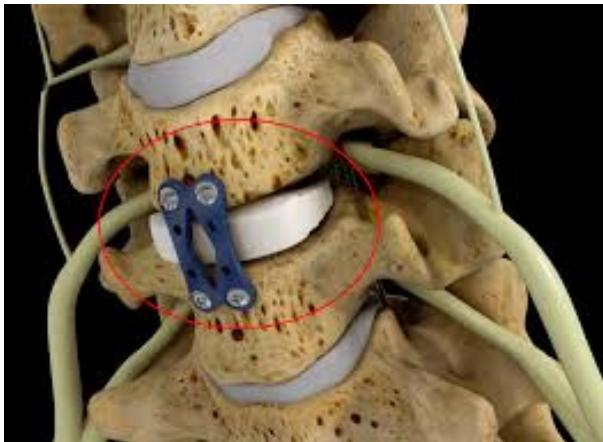

Surgical Treatment - Anterior Cervical Discectomy and Fusion: